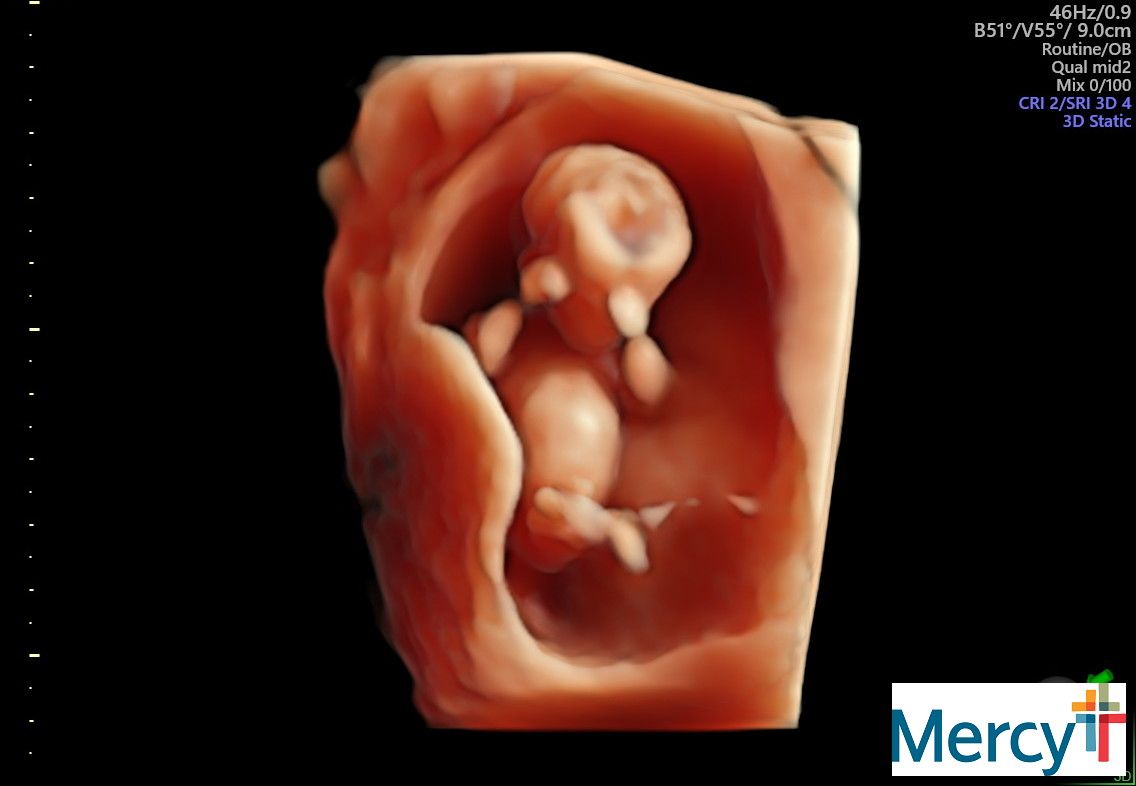

September 9: Back to Dr. Phillips!! 10 weeks

I was extremely nervous for this appointment.. Logan happened to get done with his patient early and was able to come! This was a huge relief for me. I swung down to the school and picked him up and we headed over to Mercy hospital. We went back and got our ultrasound first - and there was the cutest little bean dancing around! It was so crazy and funny to watch, it was fist bumping all around and kicking their legs. It was really great to have Log be there to actually see! We met with Dr. Phillips after, and man I love her! She has been a HUGE support to me, especially when things were really rough. She was thrilled with how things were looking and was very happy for us. We will be back in 3 weeks for another check. :)